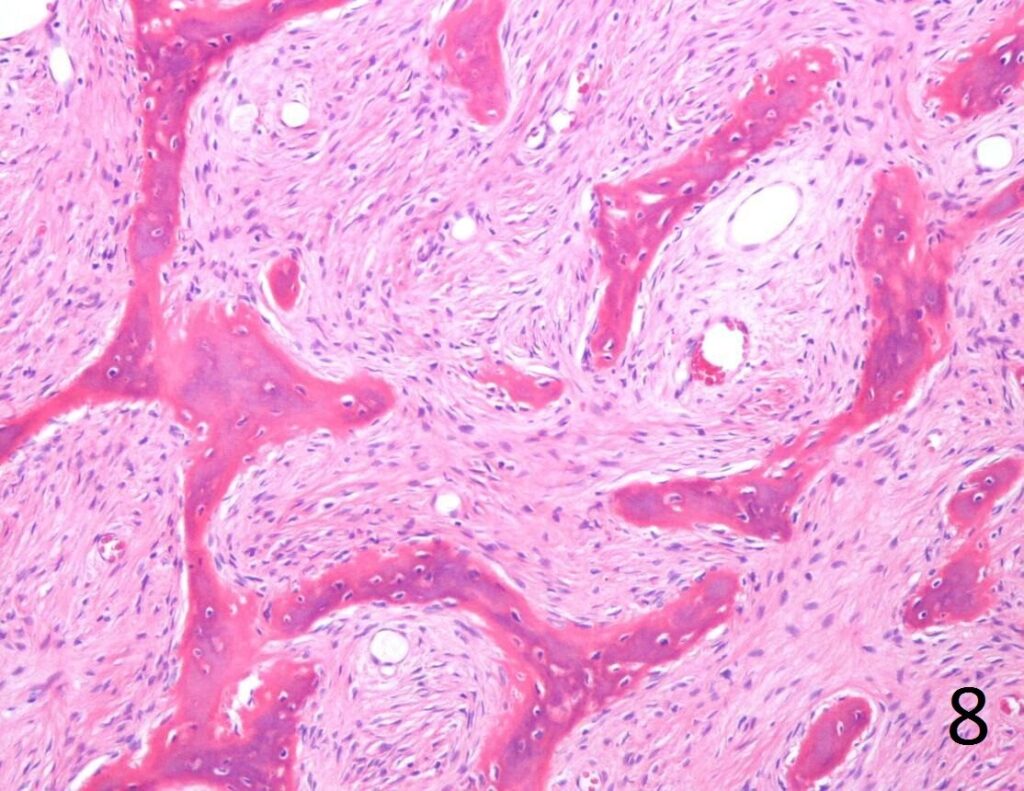

Microscopic

• Combination of bland hypocellular fibrous tissue with small fragments of woven bone without visible rimming by osteoblasts(Fig. 7-8) .

• The trabecule are common referred as Chinese characters, or resembling “Cs”and “Os”. Also may be called Alphabet Soup. This arrangement may mimic the appearance of Paget’s diseases

• Trabeculae are not lined with oteoblasts.

Fig. 8. Microscopic: Low power photograph of fibrous dysplasia shows a combination of bland fibrous tissue with small fragments of woven bone.